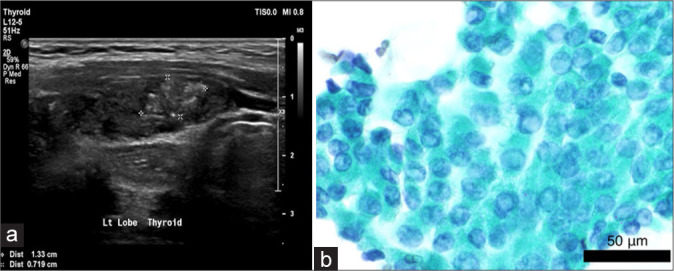

Objective: Thyroid nodules are frequently encountered in medical practice. Fine needle aspiration cytology (FNAC) is used to rule out malignant nodules, but few studies have questioned the accuracy of FNAC in larger thyroid nodules compared to smaller ones. We, therefore, aim to compare the diagnostic performance of FNAC based on nodule size and whether larger nodule size increases the possibility of obtaining indeterminate or non-diagnostic results.

Material and methods: Adult patients with thyroid nodules who underwent thyroid biopsy and surgery from 2016 to 2022 were included in the study. We assessed the proportion of benign, malignant, indeterminate, and non-diagnostic FNAC in relation to the nodule size. We then divided cytology into true positive (malignant FNAC and histology), and true negative (benign FNAC and histology) and examined whether the proportion of true FNAC would be affected by different thyroid nodule cutoffs. The study used mean and frequency to describe continuous and categorical variables. t-test and Chi-square tests were used to compare statistics.

Results: Three hundred and forty-five patients were included in the study. The majority were female (86.7%) and older than 40 years. Half had a benign histology; the other 50% were malignant. The majority (49.3%) had indeterminate thyroid cytology. The proportion of indeterminate or non-diagnostic FNAC was the same (58%) in nodules ≥4 cm and <4 cm. The proportion of true FNAC was similar between different nodule size categories. It was 35% in ≥4 cm, and 34.3% in <4 cm nodules.

Conclusion: The study found that the diagnostic performance of FNAC in thyroid nodules did not significantly differ based on nodule size, with similar rates of indeterminate or non-diagnostic results across different size categories. The proportion of true positive FNAC results also remained consistent regardless of nodule size.